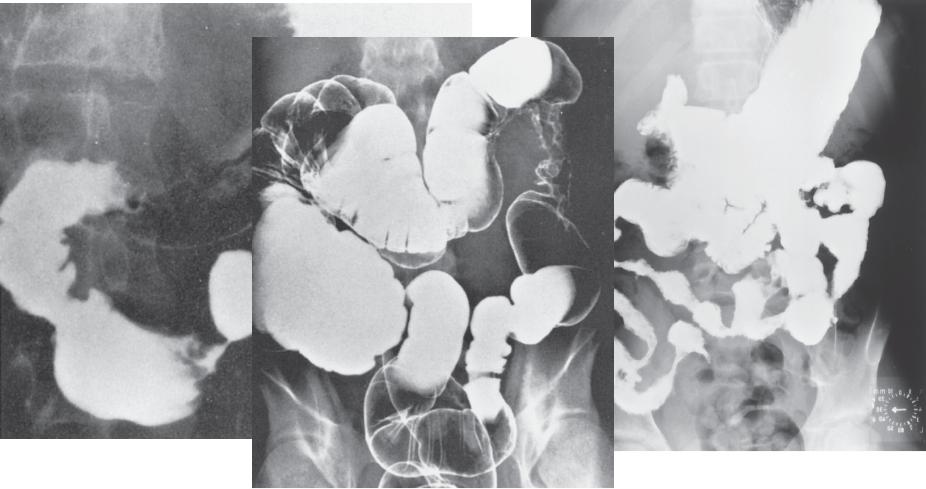

Болезнь Крона: рентгенологические признаки